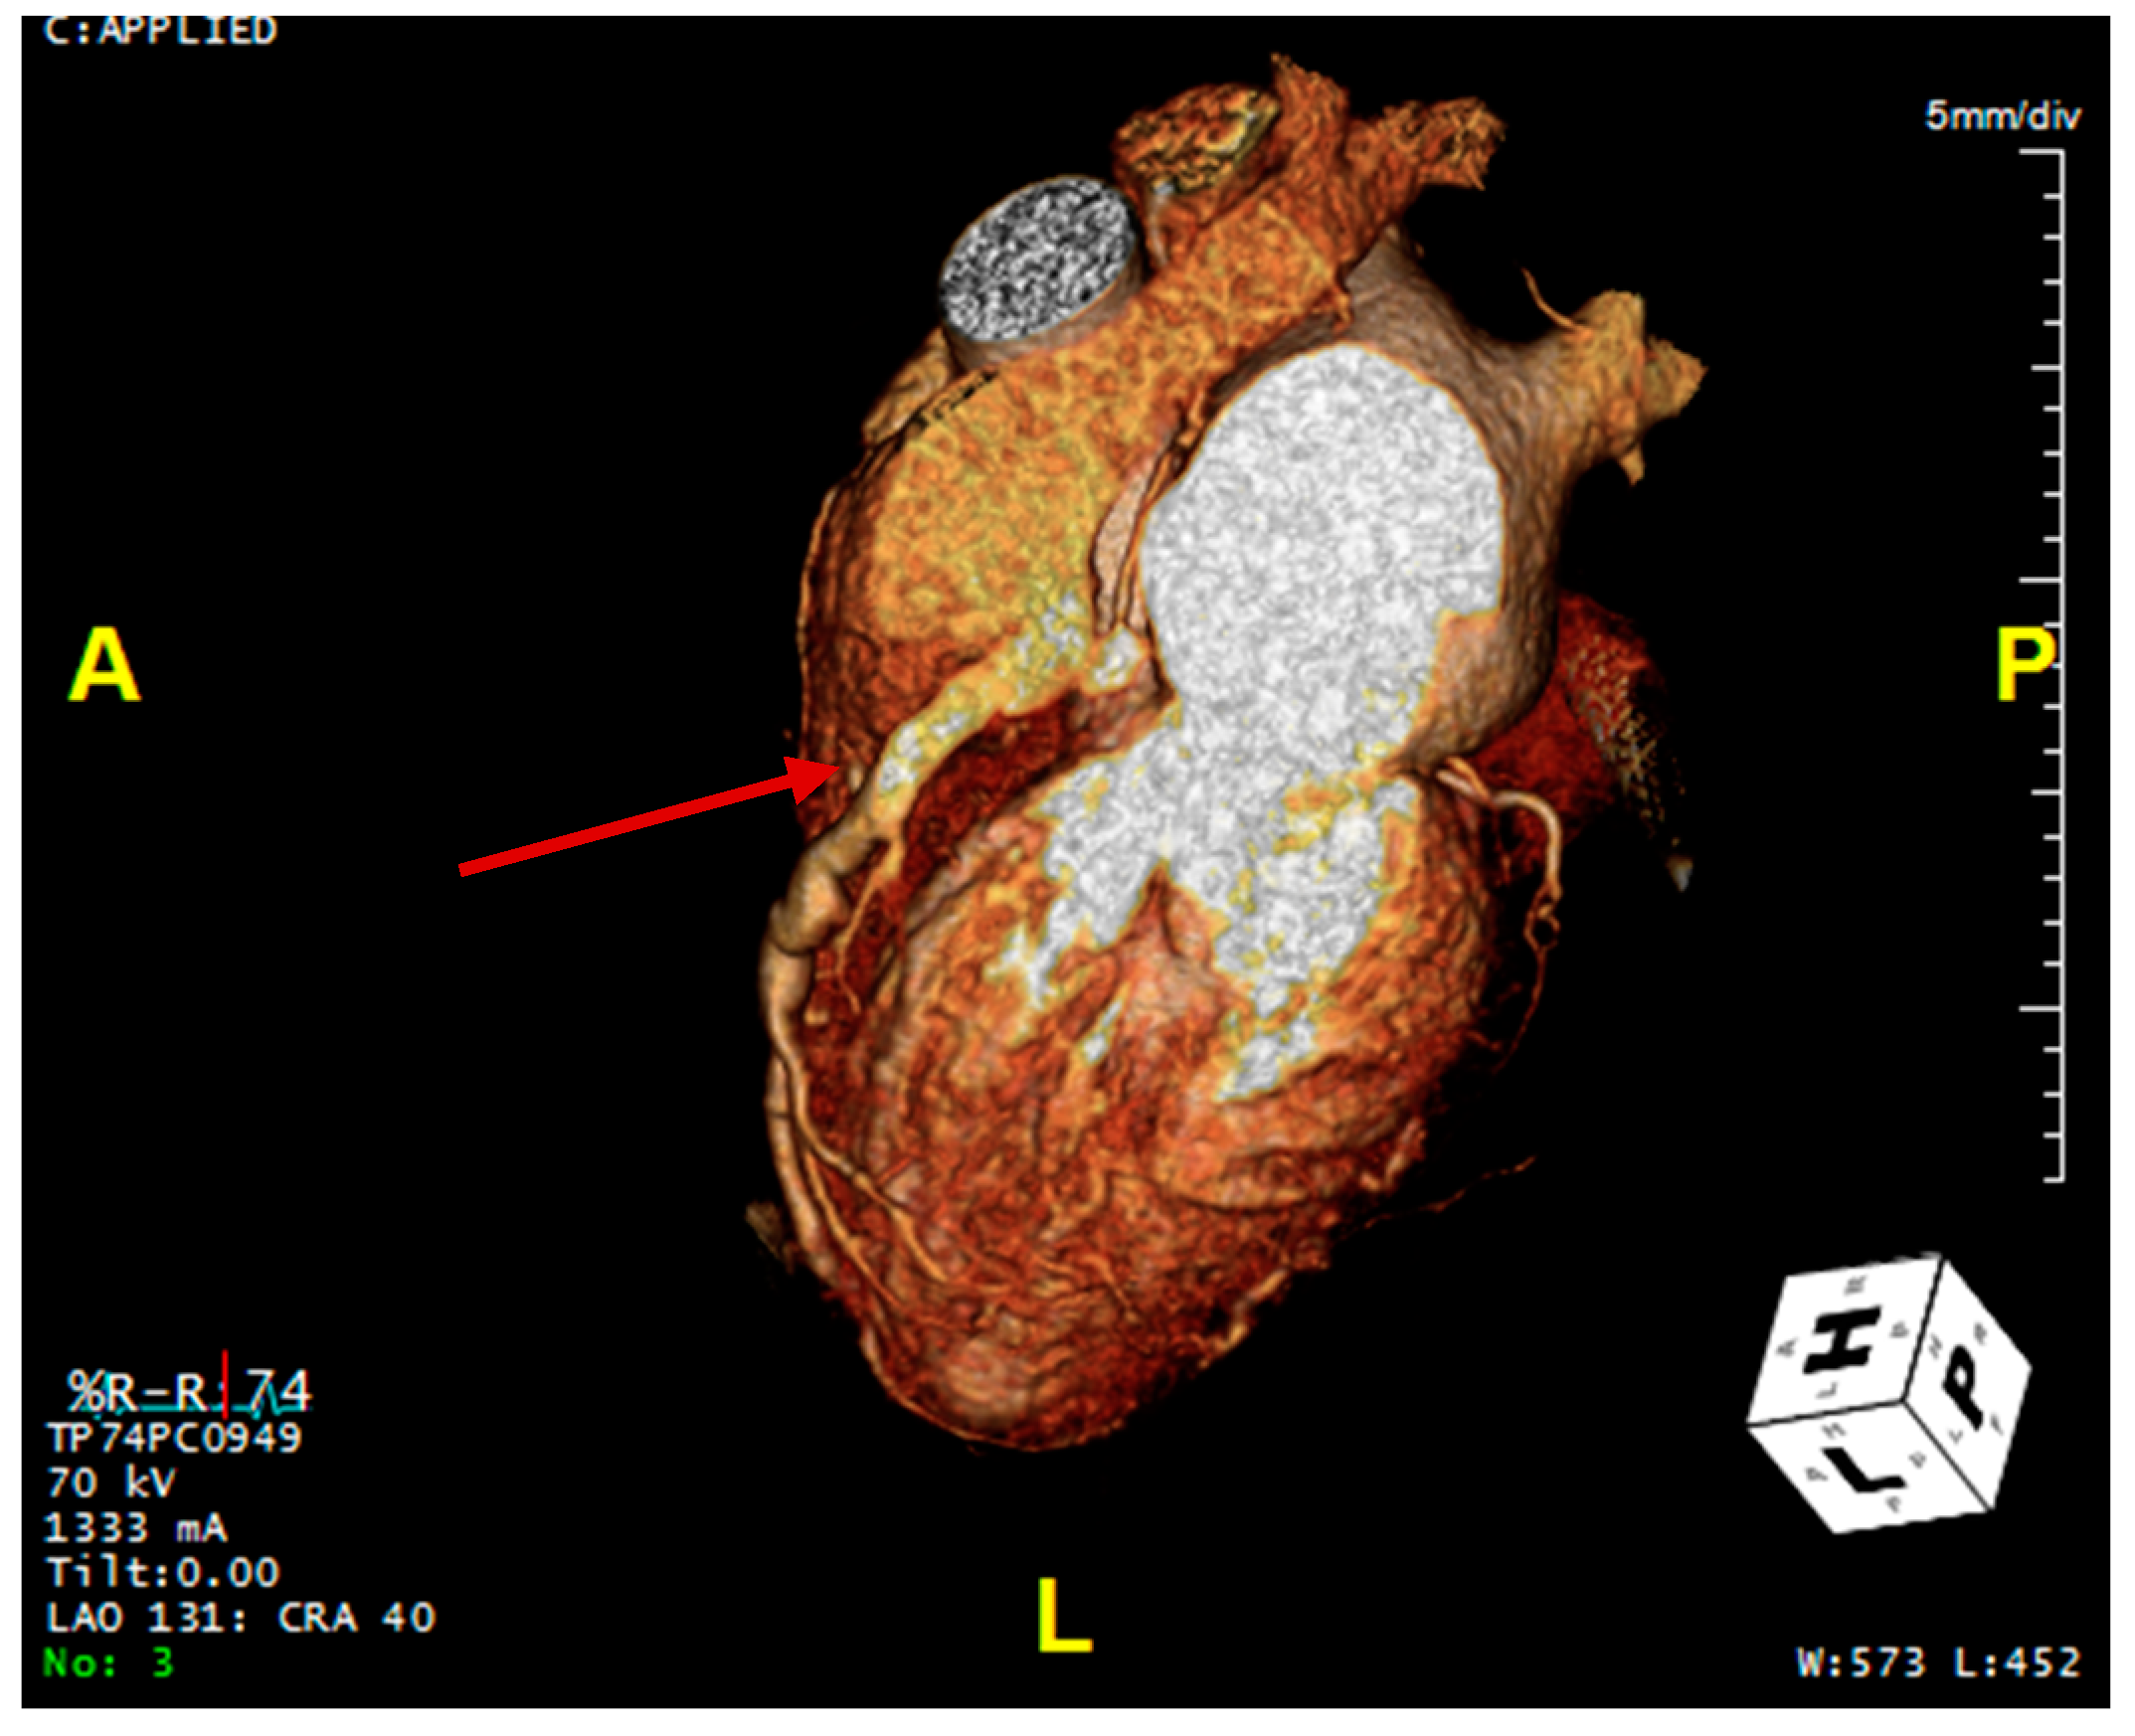

Transthoracic echocardiogram (TTE) revealed a normal ejection fraction, a mildly dilated left atrium, and no regional wall motion abnormalities. Here, there was color Doppler flow signal in the interventricular septum in both the 4 chamber and short axis view, suggestive of a restrictive muscular ventricular septal defect (Video S1). However, the presence of diastolic flow in the septum suggested against a ventricular septal defect. On further review, there was a prominent diastolic flow originating from the right coronary cusp with spectral Doppler consistent with coronary flow and possibly representing a coronary artery fistula of the RCA into the RV (Figure 2). More importantly, there was aneurysmal dilatation of the proximal RCA (1.0 cm), which had a highly tortuous course along the right atrioventricular groove into the posterior interventricular groove. Stress TTE with cardiopulmonary exercise testing (CPET) was performed, which revealed mild apical hypokinesis with exercise (Video S2). On exercise, the patient was able to achieve 4.2 metabolic equivalents (METs) and 66% of her predicted maximum heart rate prior to early termination due to the presence of anginal symptoms. Her peak oxygen consumption was 14.7 mL/kg/min (46% predicted). Subsequently, a computed tomography coronary angiogram (CCTA) was organized, which demonstrated an anomalous origin of the left main coronary artery arising from the main pulmonary artery (PA) with extensive collateralization from the aortic arch and the RCA as well as diffuse dilatation of the coronary arterial tree (Figure 2 and Figure 3).

Figure 3. Coronary CT angiogram demonstrating the dilated right coronary artery (the right coronary artery is marked by arrow).